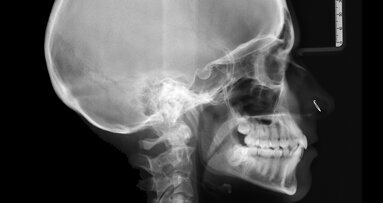

Odstranění fragmentů zlomených nástrojů pomocí Terauchi File Retrieval Kit

Následují zásadní tvrzení o odstraňování fragmentů nástrojů – mnohé z nich definované Dr. Yoshi Terauchi, který také sestavil Terauchi File Retrieval Kit (TFRK), k provádění této v minulosti náročné a nepředvídatelné procedury (obr. 1).